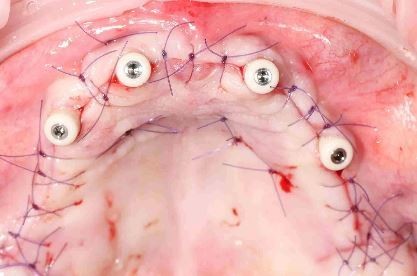

Лечение: установили два импланта на нижнюю челюсть, чтобы исключить съемный протез на нижней челюсти. На верхнюю челюсть изготовили металлокерамические коронки и съемный протез, а на нижней челюсти зубы со стираемостью восстановлены с помощью цельно-керамических коронок

Лечение: удаление несостоятельных зубов, восстановление отсутствующих зубов на имплантатах, Реконструкция улыбки с помощью цельнокерамических коронок и виниров